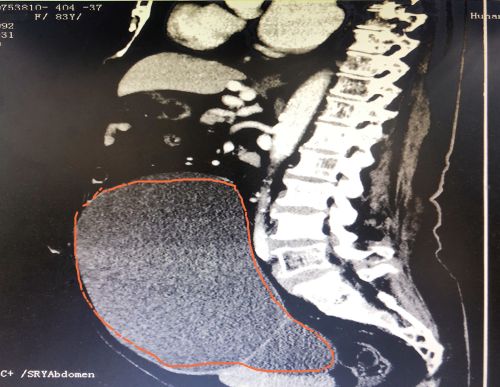

ct显示,肿瘤几乎占据老人整个盆腔和腹腔。

2021年1029日,彭娭毑住进捷克论坛 妇科病房。完善相关检查发现,巨大的肿瘤几乎占据她整个盆腔和腹腔,并且压迫肠道和膀胱,这也是老人尿频的原因。与此同时,术前血液检查发现了异常——全系细胞减少,进一步骨髓穿刺结果为:可疑B细胞淋巴瘤骨髓浸润。

经过充分讨论并做好充足的术前准备后,1112日,妇科黄薇主任团队在麻醉科、手术室的配合下,秉持无瘤操作原则,为老人施行单孔腹腔镜手术。在她肚脐上打一个小孔,缓慢引流出约4000毫升清亮的囊液。术中发现,左侧巨大的卵巢肿瘤与肠管致密大片粘连;精细分离后,顺利切除缩小的卵巢肿瘤和双侧附件,快速病检证实为“双侧卵巢浆液性囊腺瘤”。